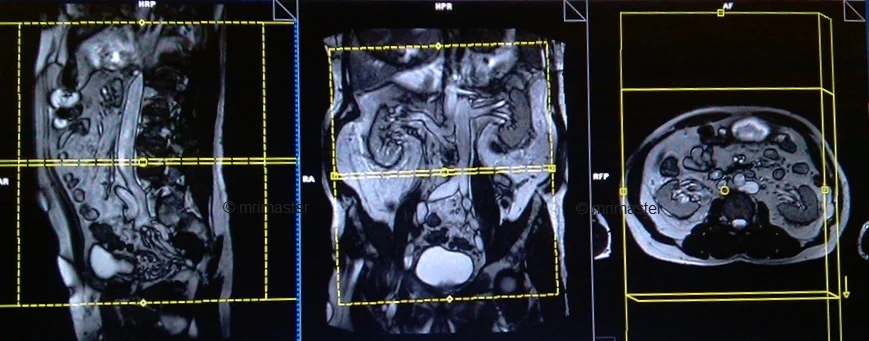

MRI Kidney Ureters and Bladder (KUB) Localizer

A three-plane T2 TRIFISP\HASTE localizer must be taken initially to localize and plan the sequences. These are fast single-shot localizers with under 25s acquisition time, which are excellent for localizing vascular structures. Take at least 5-8 slices in all planes to get the best results.

T2 HASTE\TRUFI axial 4 mm

Plan the axial slices on the coronal plane, angle the positioning block parallel to the right and left iliac crest. Check the positioning block in the other two planes. An appropriate angle must be given in the sagittal plane (horizontally across the abdomen). The slices must be sufficient to cover the entire abdomen and pelvis from the diaphragm down to the symphysis pubis. Use a field of view (FOV) that is large enough to encompass the entire abdomen, typically ranging from 350mm to 400mm.

T1 vibe DIXON 3d axial 4 mm

Plan the axial slices on the coronal plane; angle the position block parallel to the line along the right and left iliac crest. Check the positioning block in the other two planes. An appropriate angle must be given in the sagittal plane (perpendicular to the lumbar spine). Slices must be sufficient to cover the whole abdomen and pelvis from diaphragm down to symphysis pubis. FOV must be big enough to cover the whole abdomen (normally 350mm-400mm).

T1 vibe DIXON 3D coronal 2mm

Plan the coronal slices on the axial plane; angle the position block parallel to the mid line along the right and left kidneys. Check the positioning block in the other two planes. An appropriate angle must be given in the sagittal plane (parallel to L spine). Slices must be sufficient to cover the whole urinary system. Phase oversampling and, in the case of 3D blocks, slice oversample, must be used to avoid wrap around artefacts. FOV must be big enough to cover the kidneys and bladder. Instruct the patient to hold their breath during image acquisition. (In our department we instruct the patients to breath in and out twice before the “breath in and hold” instruction.).

T2 HASTE fat sat coronal 3mm